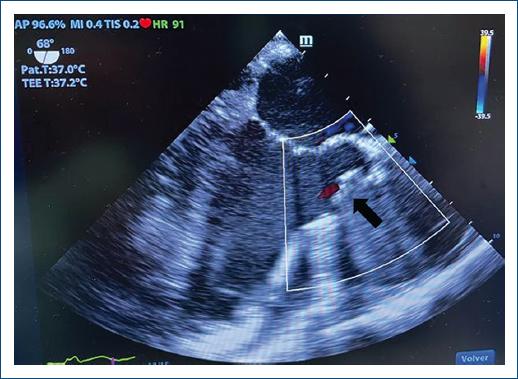

Figure 4 A control echocardiogram showed complete occlusion of the graft at the neck of the pseudoaneurysm (arrow).